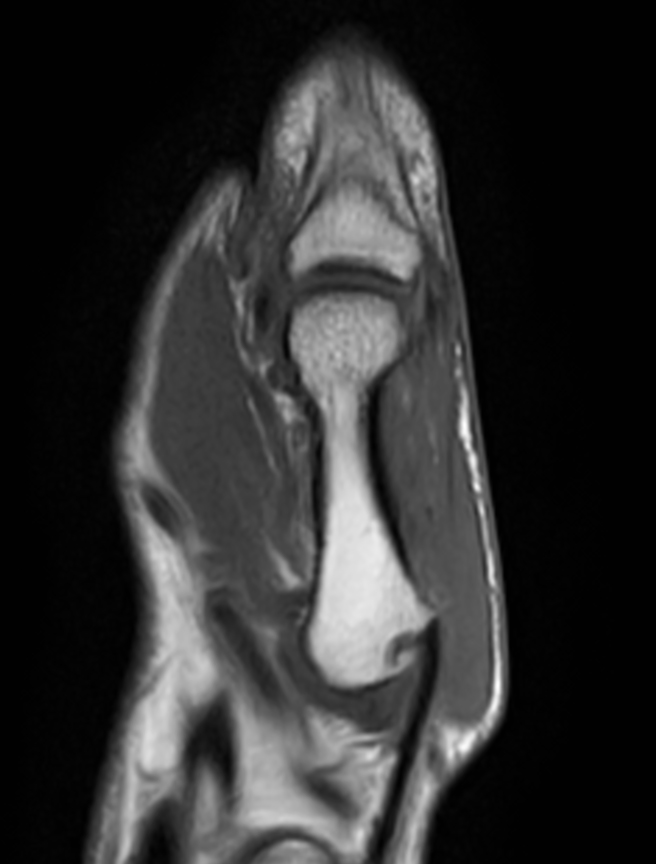

Patient with pathology on the thumb. ExamCard includes mDIXON XD TSE to achieve uniform, complete and consistent fat-free imaging. It simplifies the scan procedure by providing multiple image types in one single scan, including with/without fat suppression contrasts.

PDw TSE mDIXON XD (In Phase)